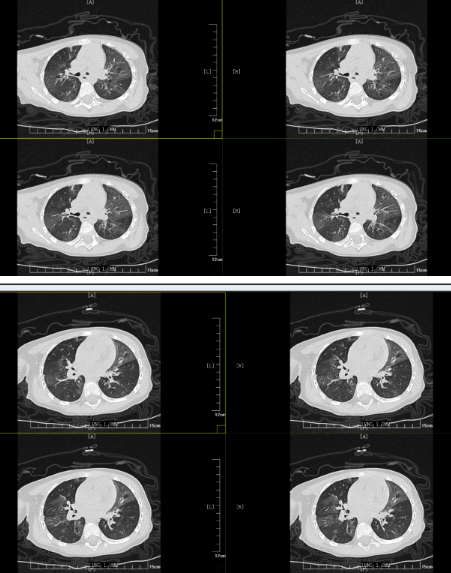

但胸部CT的結果表明小丸子的肺內病變比較重,同時通氣也不均勻,確實存在堵塞,可這個"堵住氣管的東西”到底是什么,還得在支氣管鏡檢查下才能知道。在和小丸子的父母詳細溝通病情后,入院第二天一早,小兒內科田恬主任便為其進行了無痛電子支氣管鏡檢查。